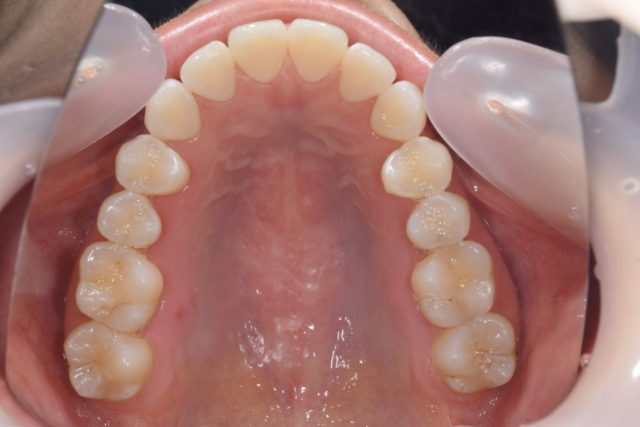

⑤お口を大きく開けて頂き、鏡で上顎の噛み合わせを写したお写真

上の歯の噛み合わせ部分や歯並びを診ることが出来ます。